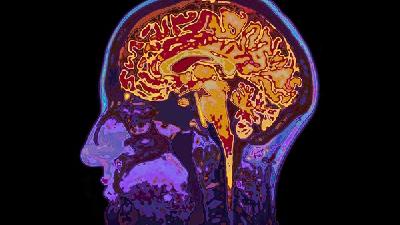

妈妈在妊娠期如果护理没有做好,可能导致宝宝出现小儿脑瘫,妊娠期是个关键时期,对妈妈和宝宝都是,妈妈最担心的也是孩子的健康问题。

小儿脑瘫对宝宝危害很大,要了解妊娠期脑瘫病因做好预防,生个健康宝宝。